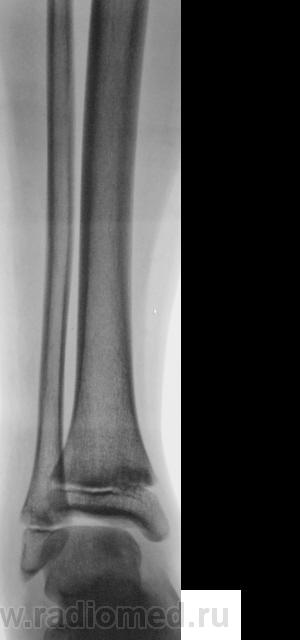

Уважаемый Валентин Львович! А что в жалобах, анамнезе? В переднемедиальной зоне дист. метафиза б/берцовой кости субхондрально под зоной роста участок уплотнения к/структуры, не отграниченный от неизмененной костн. ткани. Возможно, это импрессионный перелом? или остеонекроз? Смущает небольшой очаг аналогичной структуры в таранной кости под медиальным валом блока.

Я тоже убедительных костно-травматических изменений не вижу. если есть сомнения, снимите вторую ногу.

Алё, детские рентгенологи! Уплотнение костной структуры над зоной роста патологическое или нет?

На мой взгляд, все указанные коллегами признаки - не патологические. Травматических повреждений нет.